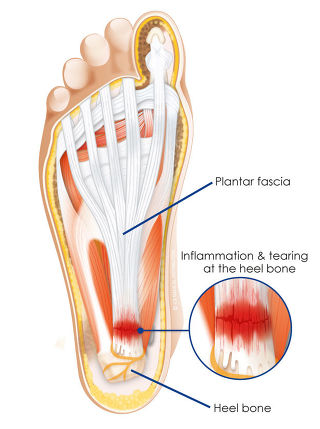

발바닥 근막(족저근막)은

중앙(그림의 1번)

외측(그림의 3번)

내측 (그림의 2번)

3가지로 구성되어있는데요.

염증은 뒷꿈치 중앙에 가장 잘 생깁니다.